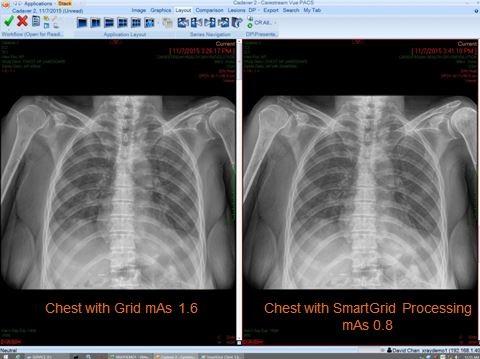

Carestream Introduces Smartgrid Software To Reduce Effects Of Scatter Radiation Imaging Technology News